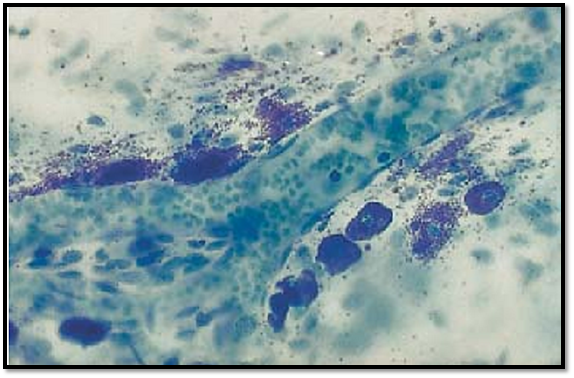

Several mast cells are lined up along a dividing arteriole. They are about 10–12 μm long and contain blue-violet (metachromatic) granules . The cell nuclei in the center are often obscure d because granules cover them. The release of mast cell granules into the extracellular space ( exocytosis) is triggered either by nonspecific stimuli or by antigen-antibody reactions. In this preparation, there are also many metachromatic granules present in the free connective tissue space. This whole-mount preparation (not a section) is from the peritoneal lining of a rat diaphragm. The arteriole contains blood cells.

Stain: toluidine blue; magnification: × 400